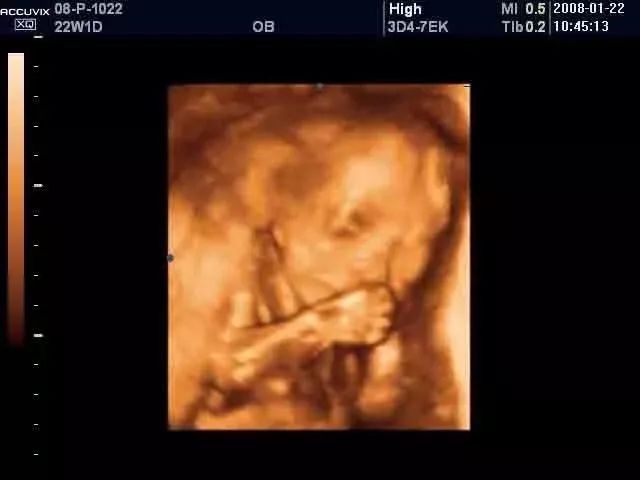

从B超中可以看出打娘胎起,宝宝就开始用吃手的方式来训练自己如何“快、准、狠”地找到妈妈的乳头啦。